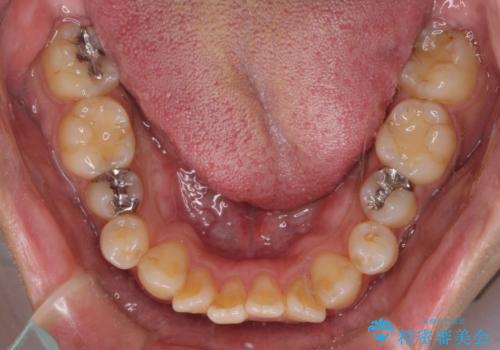

オープンバイトと目立つ銀歯 インビザライン矯正とセラミック修復治療

- 奥歯の目立つ銀歯と上下前歯の叢生と隙間を気にして来院された患者様です。

開咬の治療は、前歯を閉じるように動かすとともに、上下臼歯を圧下(骨内にめり込ませる)させることで進めて行きます。

インビザラインは臼歯の圧下を効果的に行えるため、インビザラインを用いて矯正治療を行うこととしました。

銀歯については、矯正治療により咬合関係を改善し、矯正治療後半に修復治療を行うこととしました。

修復治療後に細かい部分をインビザラインで再度仕上げるプランとしました。